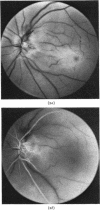

When axoplasmic transport in ganglion-cell axons is interrupted by ischaemia organelles accumulate in distended axon terminals at the edges of the infarct. This report illustrates the localized opaque swelling of nerve fibres shich develops at or near the optic disc after occlusion of the central retinal or posterior ciliary arteries. No such swelling occurs in patients who have a combined occlusion of these vessels.